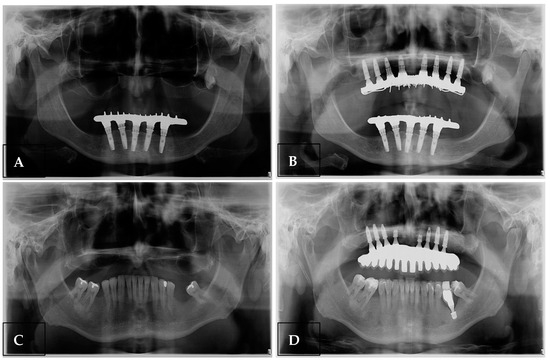

Panoramic radiographs taken before and after the procedure demonstrated an increase in alveolar ridge height following grafting, which enabled the placement of eight implants in the atrophic maxillae of two patients (Figure 4).

Figure 4. Panoramic radiographs of two clinical cases, (A,C) initial radiographs and (B,D) radiographs with the implants installed in the grafted areas 5 months after surgery.